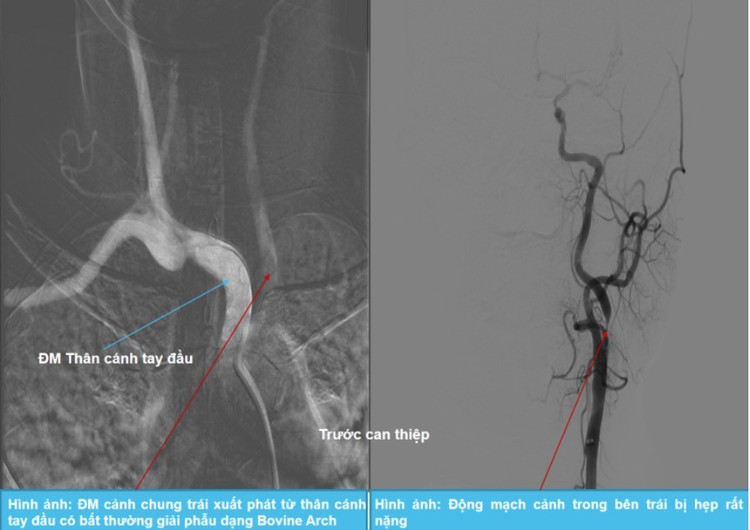

Bệnh nhân được chỉ định chụp mạch xóa nền DSA, cho thấy động mạch cảnh trong bên trái bị hẹp rất nặng, trong khi động mạch cảnh trong bên phải bị teo nhỏ – nguyên nhân chính gây thiếu máu não – kèm bất thường giải phẫu mạch máu dạng Bovine Arch (dạng động mạch cảnh chung trái xuất phát từ thân động mạch cánh tay đầu thay vì từ cung động mạch chủ như bình thường).

Các bác sĩ quyết định thực hiện can thiệp đặt stent để tái thông dòng chảy mạch máu não cho bệnh nhân.